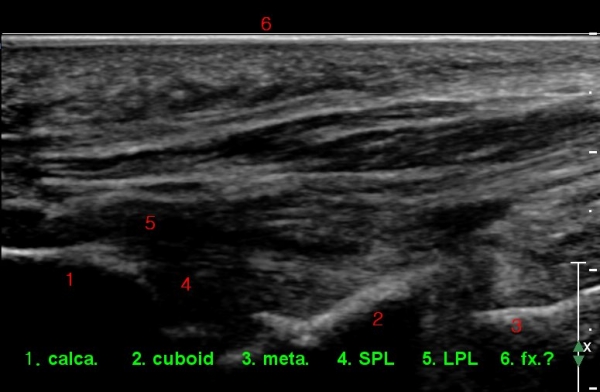

Á¾°ñÀÔ¹æ°ñ°üÀý Á¾´Ü¸é°Ë»ç»ó Á¾°ñ Àü¹æµ¹±â °ß¿­°ñÀý°ú Á¦4ÁßÁ·°ñ °ß¿­°ñÀýÀÌ °üÂûµÈ´Ù(»çÁø 2).